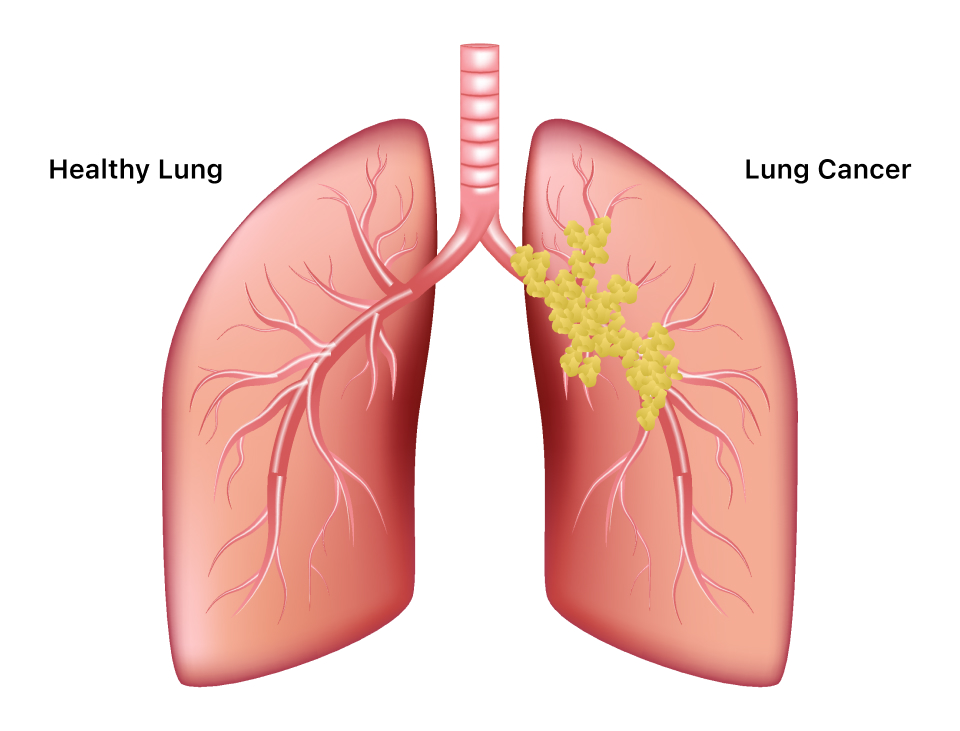

Lung Cancer:

Lung cancer is a serious health condition affecting various regions of the lung. Early diagnosis and appropriate treatment strategies are essential for enhancing prognoses. Treatment options may involve surgery, radiation therapy, chemotherapy, and targeted therapies.